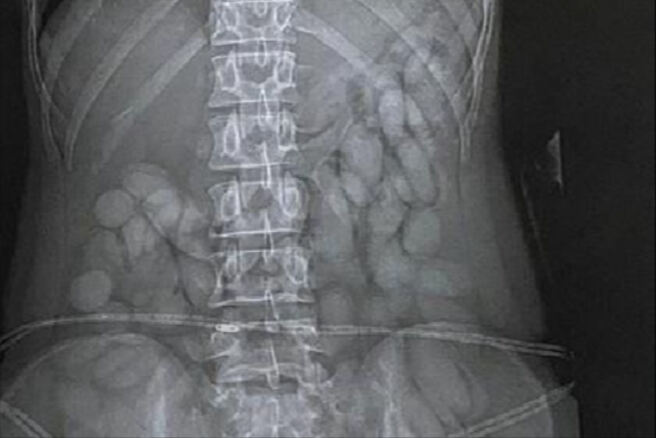

경찰은 브라질 상파울루에서 도착한 이 여성을 병원으로 보내 엑스레이 촬영을 한 결과 뱃속에서 다량의 타원형 캡슐을 확인했다.

아틀렌다 마테 남아공 경찰 대변인은 "첩보에 따라 마약운반책을 기다리고 있다가 이민국 통과 즉시 검거했다"며 "코카인이 담긴 캡슐 60여개를 회수했다"고 말했다.